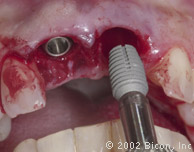

Формирование ложа имплантанта

Paralelling Pins

Pilot drill

Osteotomy

Curette